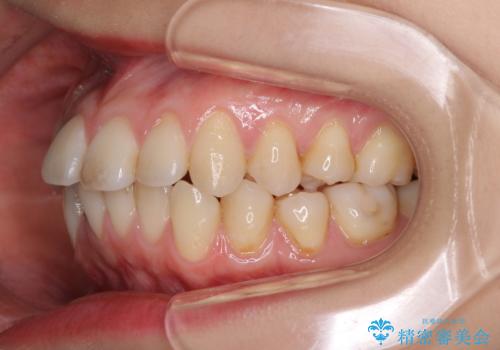

- 上下前歯のデコボコを気にして来院された患者様です。

インビザラインによる上下歯列の側方拡大と後方移動、IPR(歯と歯の間を削る)にるスペースの獲得により歯列を整えることとしました。

1日22時間の装着時間をしっかり守ってくださったので、予定していた1年よりも早く治療を終えることができました。

インビザライン矯正特有の奥歯がしっかりと咬合しない感覚も改善され、大変満足していただきました。